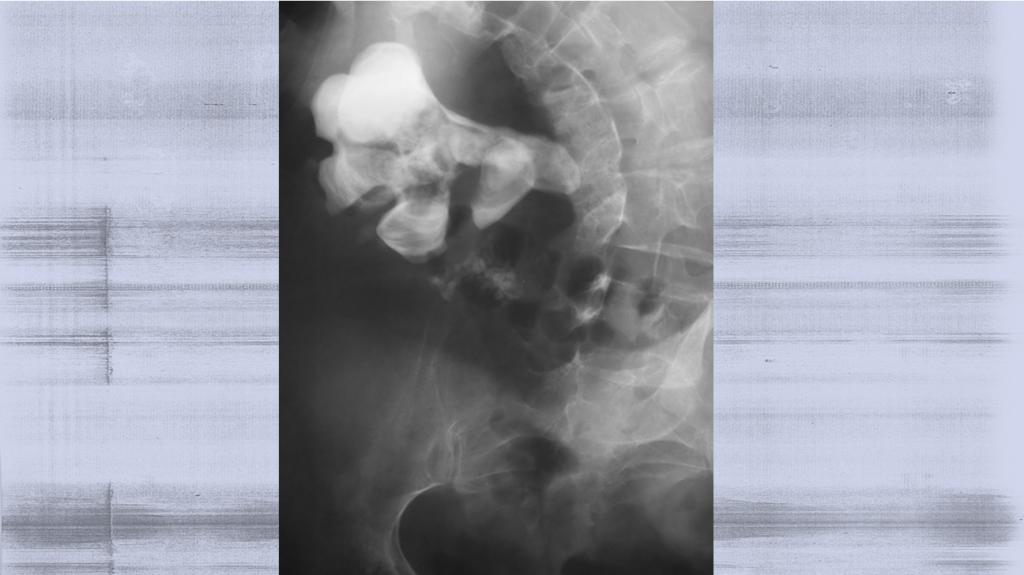

Staghorn kidney stones, also called staghorn calculi, are large kidney stones that take on a branched shape, often filling the renal pelvis and extending into the calyces of the kidney. These stones are typically made of struvite, a compound formed by magnesium ammonium phosphate, and are often associated with urinary tract infections (UTIs) caused by bacteria that produce the enzyme urease.

Struvite stones, often seen in staghorn kidney stones, are typically caused by bacterial infections in the upper urinary tract. These stones grow quickly and can become quite large, making them difficult to pass naturally. They are primarily composed of magnesium ammonium phosphate and are associated with chronic UTIs.

PCNL is considered the gold standard for treating large kidney stones, particularly staghorn stones. This surgical procedure involves a small incision in the back to access the kidney and break up the stone using specialized tools. PCNL has a high success rate and is usually the preferred method for removing large stones.